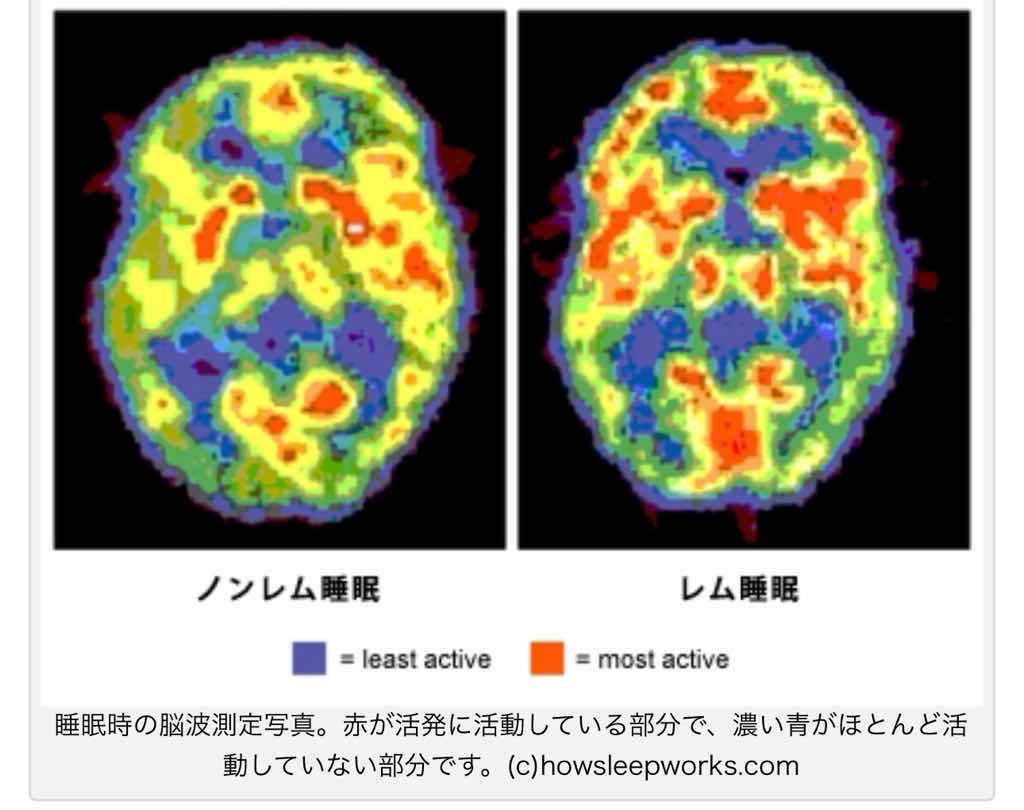

勉強してるときも寝てる時も脳の消費するエネルギーは大差ない

脳が活発に動いてる